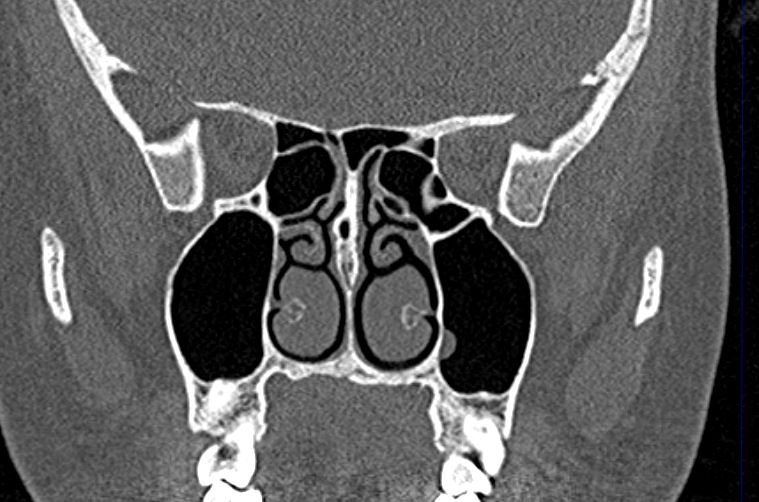

Мультиспиральная компьютерная томография дает информацию о состоянии полости носа, носовой перегородки, степени воздушности околоносовых пазух, путей дренирования синусов, состоянии слезных каналов. Сканирование позволяет оценить толщину слизистой, наличие патологического содержимого в просвете пазух (уровня «жидкости»), выявить опухолевые образования. С помощью КТ можно провести точную диагностику травматических повреждений костей лицевого черепа, определить локализацию инородных тел, попавших в полости синусов.

С помощью объемной реконструкции можно перед оперативным вмешательством увидеть особенности анатомии ЛОР-органов, определить точное расположение патологического очага по отношению к окружающим тканям. Компьютерная томография помогает в диагностике аномалий развития придаточных пазух носа, слезоотводящих каналов.